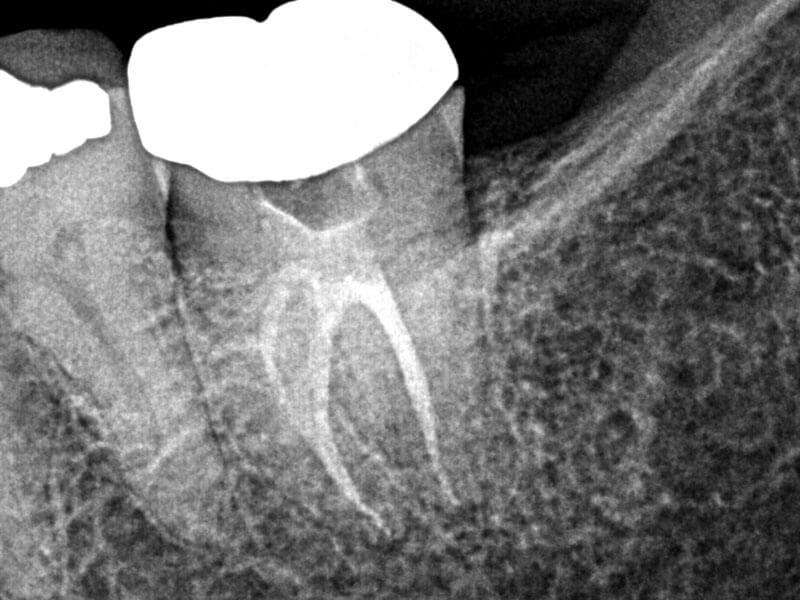

66-year-old female presented with history of spontaneous, intermittent pain in the lower left quadrant for three days, progressing to acute pain. No hot, cold or biting pain. Clinical testing revealed teeth in LLQ were negative to percussion, biting and grinding. Tooth #18 tested negative to cold, and other teeth in quadrant tested within normal limits to cold. Diagnosis: #18 necrosis and normal periapex. Treatment plan: RCT #18. Accessed, working length established, SlimShaper® ZS1 and ZS2 in distal canal and one mesial canal. Other mesial canal would not permit rotaries due to angle, so employed #15 hand file to length. GentleWave® Procedure with ProControl™ completed. Obturated with TruNatomy® 20 GP and BC Sealer HiFlow™. BC Liner™ over orifices.

Pre